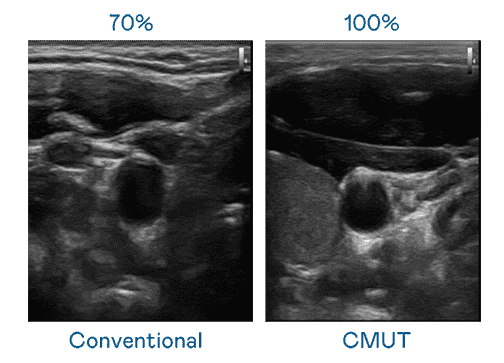

CMUT 技术是一种用电容式微机电元件来产生超音波讯号的技术。。。。与传统 PZT 压电式技术相比,,,CMUT 频宽增加 30%,,,更宽频的超音波讯号让影像解析度大幅提升,,,,是实现高影像品质医疗超音波扫描、、促进精准医疗发展的关键技术。。。

大频宽带来超清晰影像

超音波影像的解析度高低,,,,首先取决于探头能发出的讯号频宽。。。。z6尊龙 CMUT 可提供高清晰的超音波讯号,,,,提供高频宽、、高灵敏度、、、影像纹理细节更高的超音波影像,,,,协助医护人员缩短影像判读时间及利用精准的医疗影像进行诊断。。